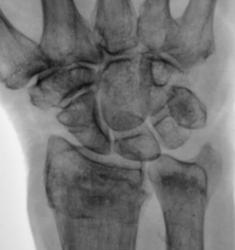

Разгибательная деформация, захождение. Функциональность кисти - тут решит травматолог. Без первичного снимка судить сложно - к примеру, состояние отломков было более удручающим, и в настоящий момент динамика положительная.

Инконгруэнтность в кистевом суставе после репозиции чревата артрозом. Необходимо решать вопрос об оперативном лечении.